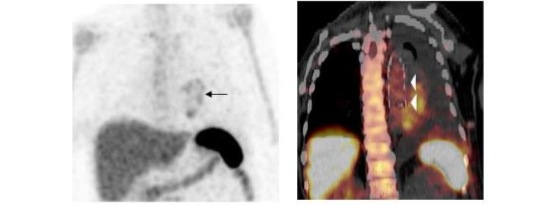

The sensitivity of WBC imaging for prosthetic vascular graft infection exceeds 90% in most investigations and is not affected by antibiotic therapy or duration of symptoms. Specificity is more variable, ranging from about 50% to 100%¹⁰. The accuracy of the test is improved by performing SPECT/CT. In one investigation SPECT/CT was 100% accurate for diagnosing infection and was useful for detecting, localizing, and defining the extent of infection (Figure 8)²¹.

Figure 8.

Infected aortic graft. Note the increased labeled leukocyte uptake in the left chest (arrow) on the maximum intensity projection (left). On the coronal SPECT/CT image (right), this activity is within the aortic graft (arrowheads).